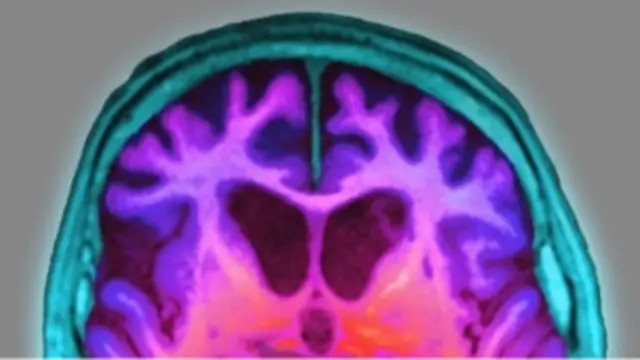

الزائمر کے جراثیم کے خاتمہ کا کامیاب تجربہ

ایک تحقیق میں چوہوں پر کینسر کے علاج کے لیے ایک دوا کے استعمال سے الزائمر کے تباہ کن جراثیم تیزی سے ختم ہوگئے۔

جرنل سائنس جریدے میں شائع ہونے والی امریکی تحقیق میں کہا گیا ہے کہ دوا کے استعمال سے چوہوں میں تباہ کن جراثیم غیر متوقع تیزی کے ساتھ ختم ہوتے گئے۔ اس تحقیق کے دوران یہ بھی معلوم ہوا کہ دوا کے استعمال سے دماغ کے افعال میں بھی بہتری آئی۔

الزائمر کا اصل سبب اب تک معلوم نہیں ہوسکا ہے لیکن خیال کیا جاتا ہے کہ یہ ایک پروٹین کے جمع ہونے سے ہوتا ہے جسے بِیٹا ایملوئڈ کہتے ہیں۔ دماغ میں یہ جمع شدہ ذخیرہ آخر کار حافظہ کے مسائل کو جنم دیتا ہے جس سے سوچنے کی صلاحیت متاثر ہوتی ہے۔